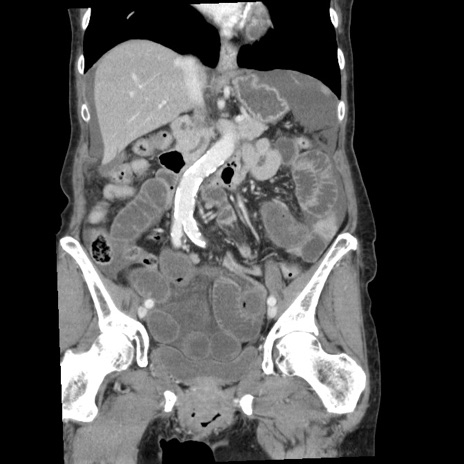

症例1(冠状断像)

【症例】80歳代女性

【主訴】腹痛

【現病歴】8時間前から腹痛あり来院。

【既往歴】糖尿病、脂質異常症、子宮体癌にて子宮全摘術

【身体所見】意識清明・会話良好だが腹痛で苦悶様、全腹部にわたって反跳痛と圧痛あり

【データ】WBC 13600、CRP 0.14、LDH 224、CK 90